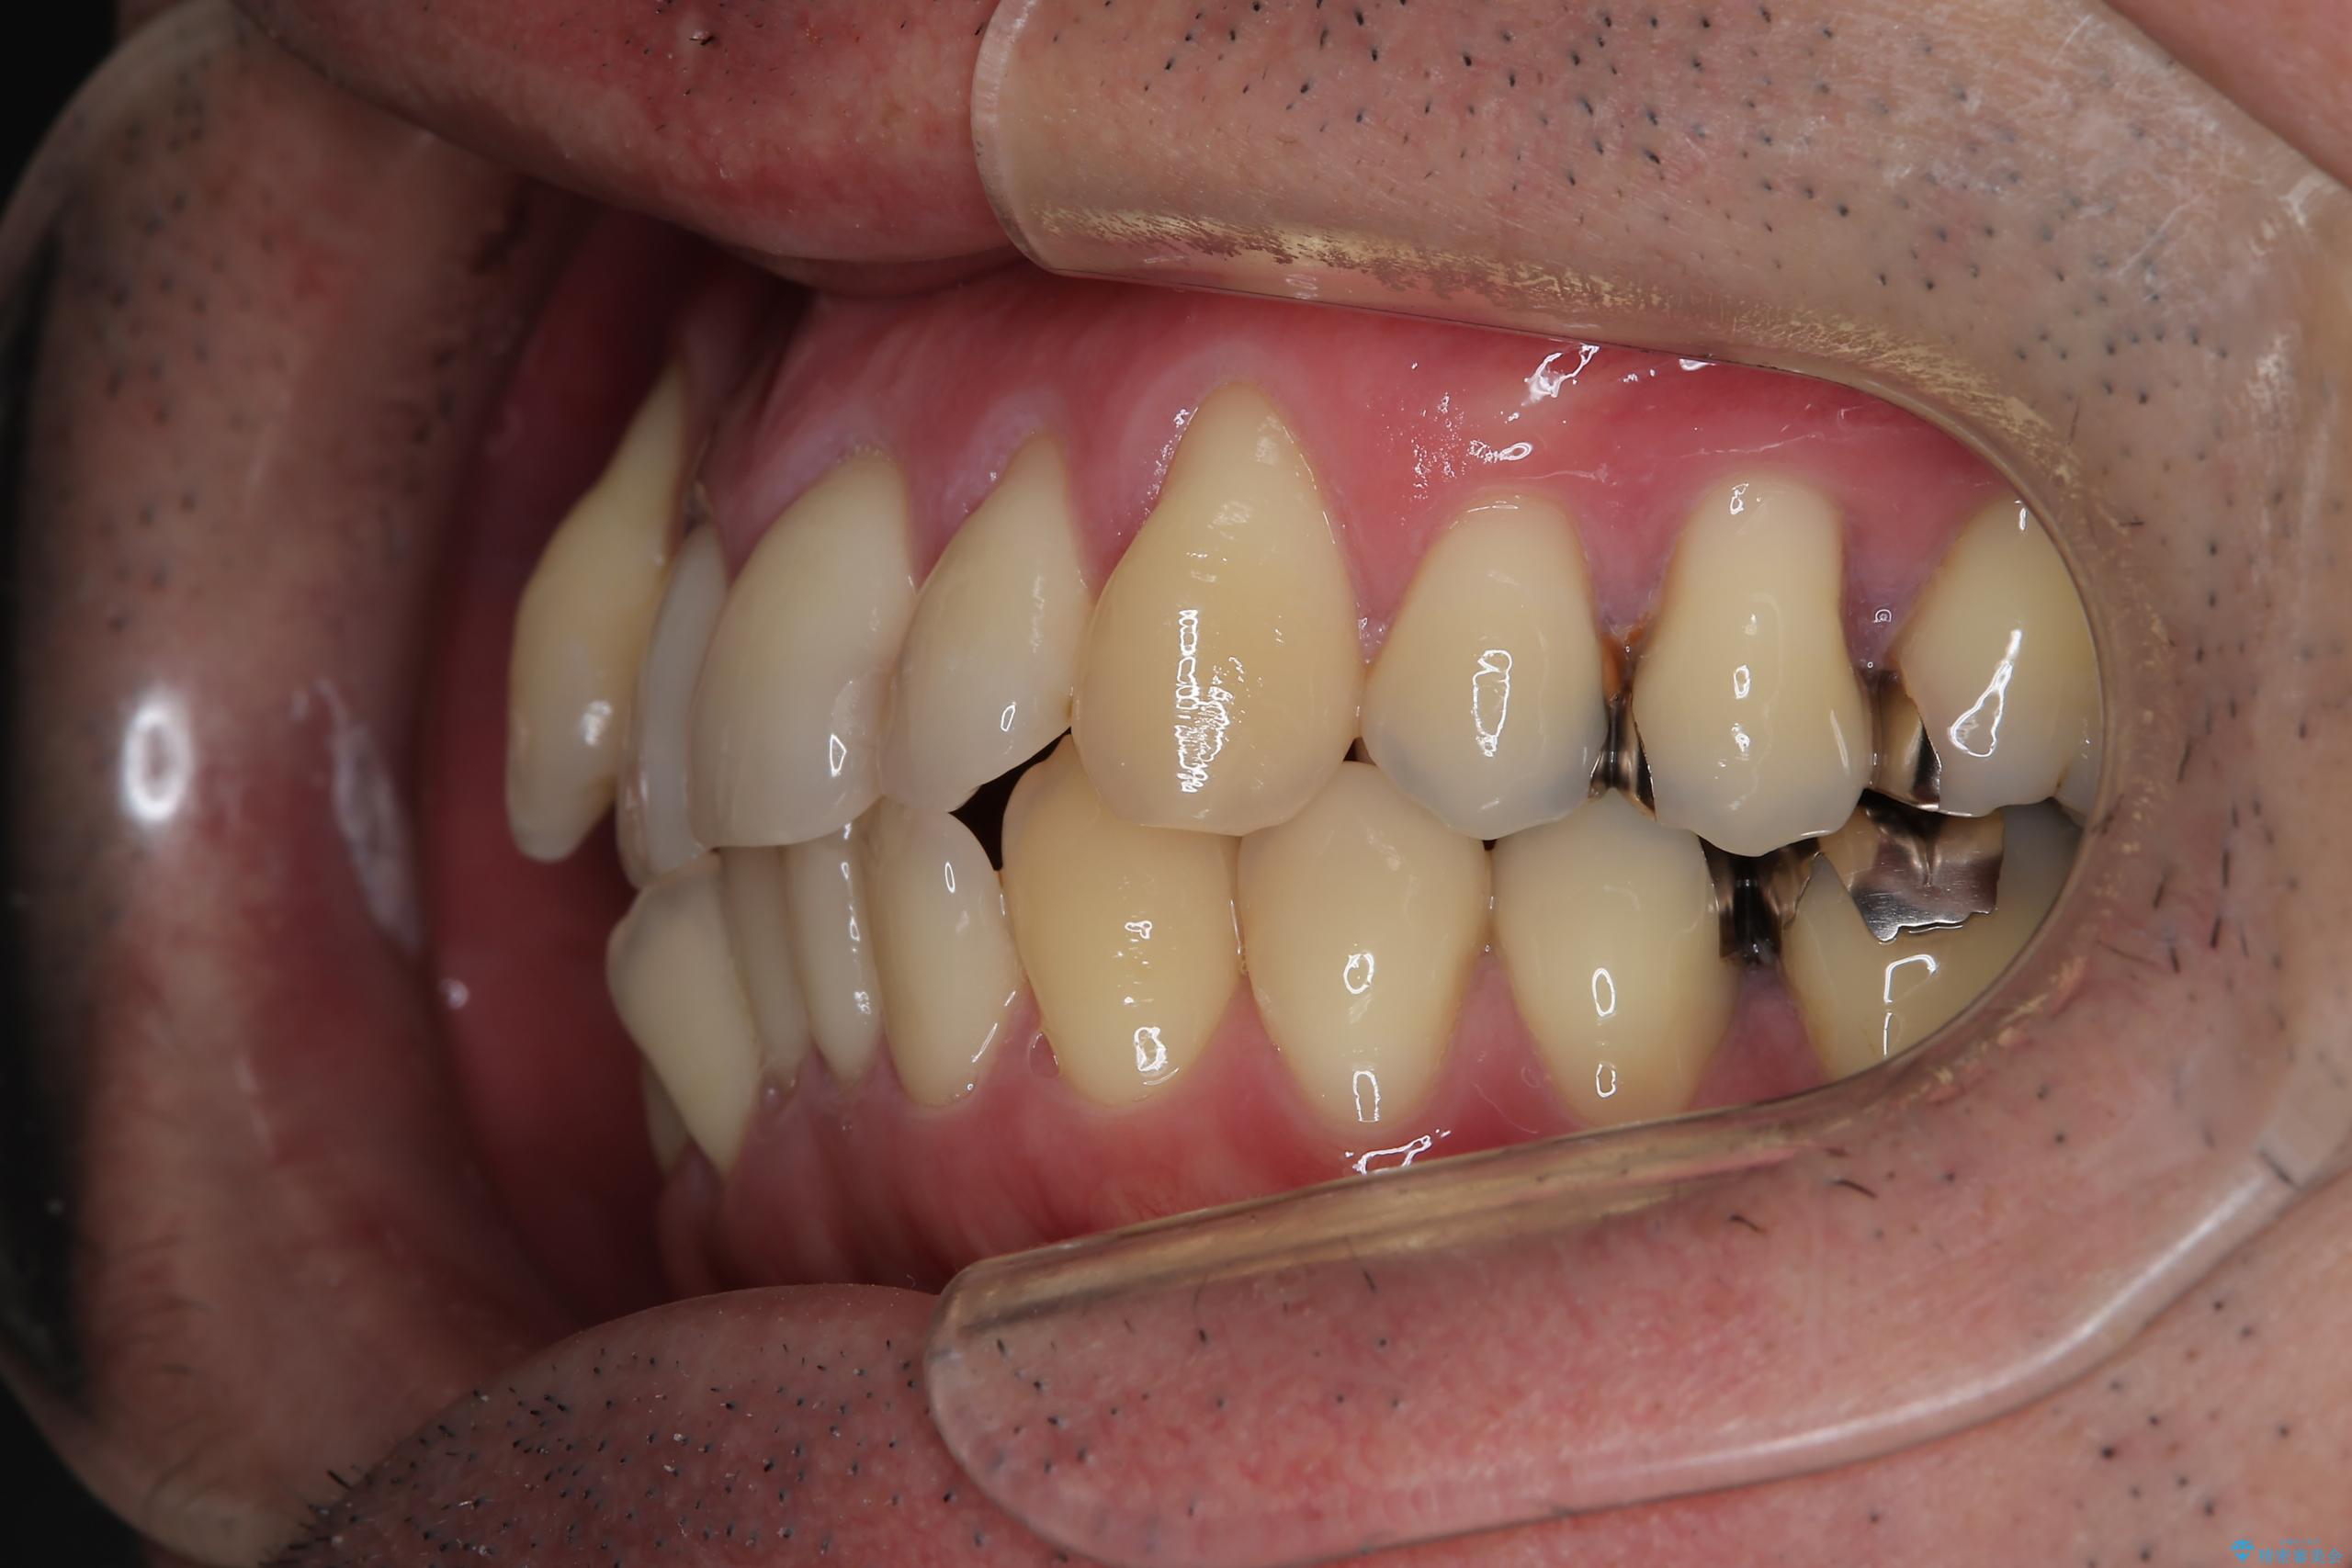

- 右上2番目の歯が舌側転位していることと前歯の叢生(がたつき)を主訴に来院されました。

右上の犬歯が初診時よりかなり歯根露出しており、矯正の力をかけるとさらに歯根露出するリスクがあるため、右上の2番目の歯を前に出すためにも

右上の犬歯を抜歯して歯並びを整える治療計画を立てました。